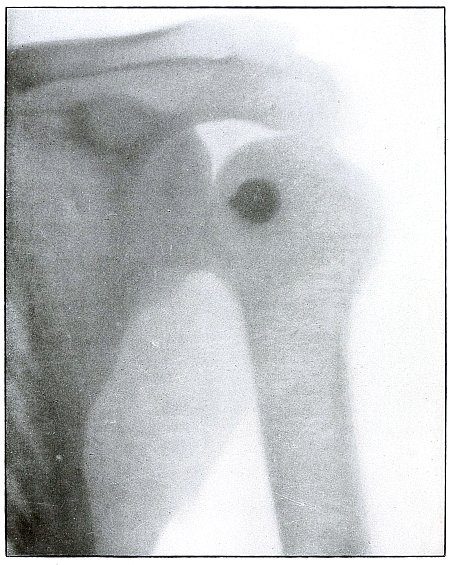

Plate 9.

_

[Pg 29]

Rifle—Plate 9.

UPPER EXTREMITY.

Gunshot Fracture of the Right Humerus, with Lodgment of the Missile.

Wound of entrance, antero-external aspect of upper third of arm.

Wound of exit, none.

The missile, deformed by ricochet, struck the bone with greatly reduced velocity and without sufficient energy to perforate the bone by which it was deflected slightly from its course and lodged in the arm.

This is something of the same effect that might have been caused by a shrapnel ball, under the same ballistic conditions with a normal shrapnel velocity giving about the same penetrating force.

The wound, without infection, is in the first week or two of repair, before any callus has formed.

Treatment is expectant.

Results favorable. [Pg 30]